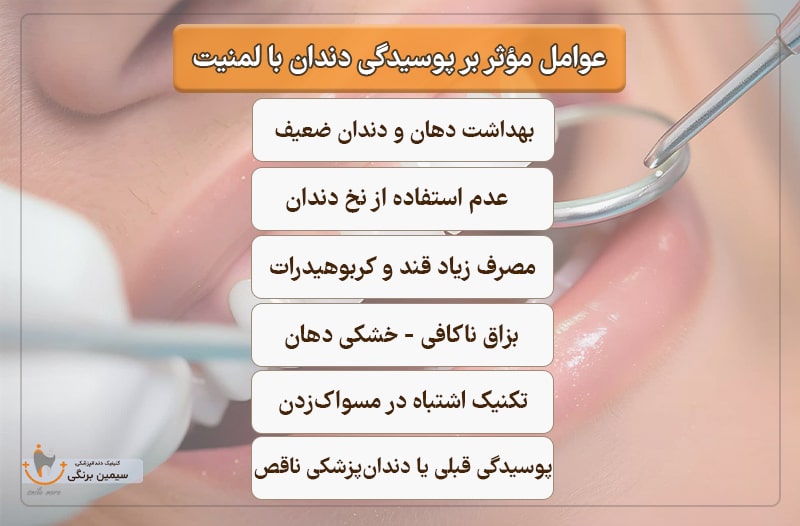

عوامل مؤثر بر پوسیدگی دندان با لمینیت

۱. بهداشت دهان و دندان ضعیف

عدم مسواک زدن منظم و درست، باعث تجمع پلاک و باکتری روی دندانها میشود که محیط مناسبی برای شروع پوسیدگی ایجاد میکند

۲. مصرف زیاد قند و کربوهیدرات های ساده

غذاها و نوشیدنیهای شیرین، غذای اصلی باکتریهای دهان هستند. با مصرف قند، اسید تولید شده توسط باکتریها مینای دندان را تخریب میکند.

۳. عدم استفاده از نخ دندان

پلاکهایی که بین دندانها باقی میمانند با مسواک پاک نمیشوند. عدم نخدندان کشیدن، شانس پوسیدگی بین دندانی را افزایش میدهد.

۴. بزاق ناکافی (خشکی دهان)

بزاق نقش حیاتی در شستوشوی باکتریها و خنثیسازی اسید دارد. خشکی دهان میتواند سرعت پوسیدگی را افزایش دهد، بهخصوص در بیماران دارای لمینت.

۵. پوسیدگی های قبلی یا دندانپزشکی ناقص

ترمیمهای قدیمی، لمینتهای ناسازگار یا تاجهای دندانی نامناسب میتوانند باعث گیر کردن غذا یا نفوذ باکتری شوند.

۶. تکنیک اشتباه در مسواک زدن

مسواکزدن افقی یا خیلی سخت میتواند به لثه آسیب زده و باعث تجمع پلاک در لبههای دندان و زیر لثه شود.